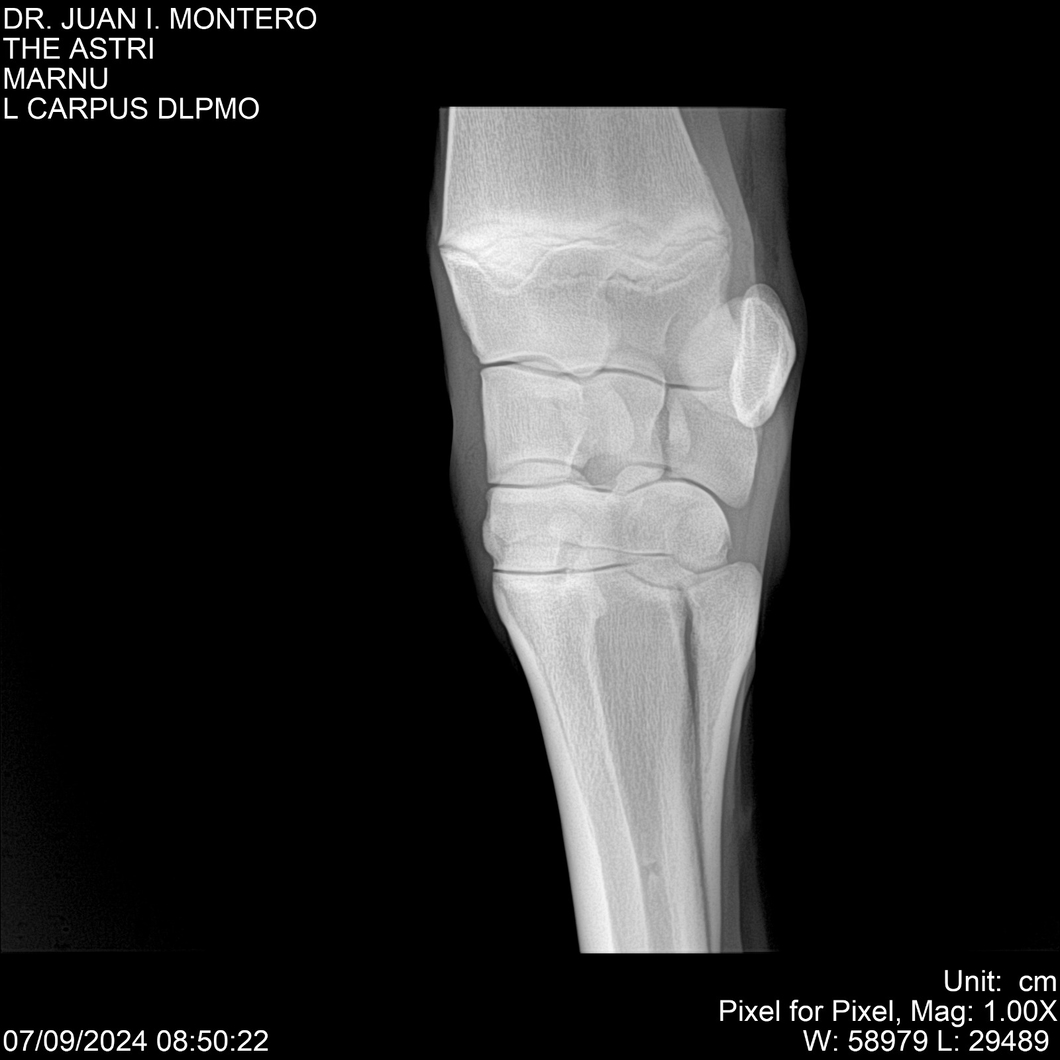

LOTE 10, THE ASTRI Lote Anterior Volver al remate Lote Siguiente Ficha Contacto Montevideo - Ficha del Lote Identificador: #282514 Categoría: Yeguarizos Montevideo - 60 Visualizaciones ClicData Contacto Empresa: Abelenda N. R., Walter Hugo Nombre*: Teléfono* : E-mail* : Mensaje Enviar Registrese gratis Este contenido Exclusivo está disponible sólo para usuarios registrados Ingresar